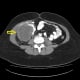

After her healthy baby boy was born, Rowsome had two CT scans and a colonoscopy, performed by gastroenterologist Ramsey Daher. All pointed to suspected colon cancer.

Doctors reviewed her imaging and colonoscopy results, and the multidisciplinary team at the Kimmel Cancer Center at Sibley charted out the best course of treatment: surgery and post-surgery chemotherapy.